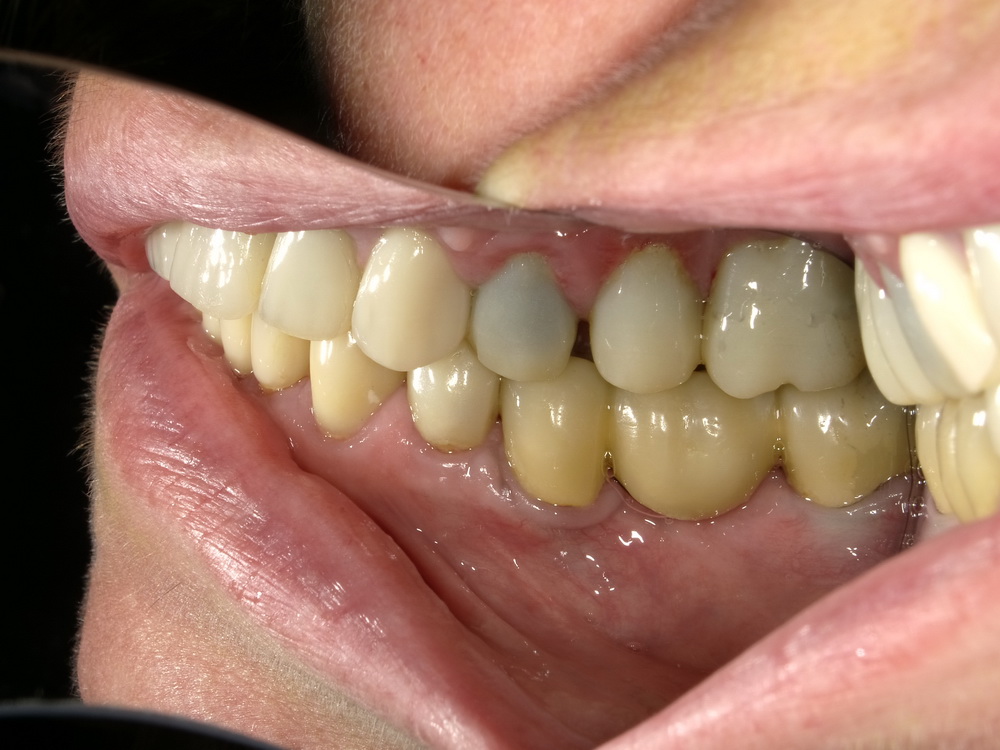

Nach mehreren Monaten Erprobungszeit der funktionstherapeutisch eingestellten Bisslage beginn nunmehr die Umsetzung der Versorgung mit Laborgfertigten Dauerprovisorien in eine Versorgung mit definitiven zahntechnischen Kronen.

Die neue Versorgung beginnt mit der Entfernung der Dauerprovisorien im Unterkieferseitenzahnbereich.